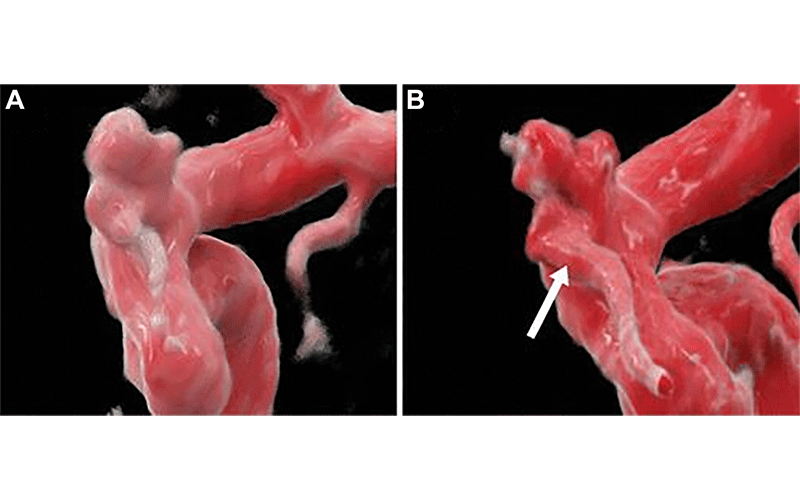

The second runner-up for the 2023 Top Images in Radiology is the publication entitled “Cerebral Aneurysm Imaging at 7T with Use of Compressed Sensing” by Amit Desai and Erik Middlebrooks (3). The authors’ direct comparison of the MR angiogram time-of-flight assessments at 7T versus 1.5T of an intracranial aneurysm (Fig 3) is an illustrative example of the incremental benefit that higher-field-strength MRI can offer, when available.